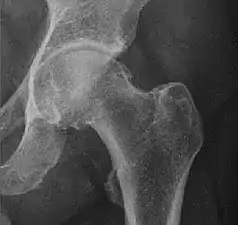

Adults

Landmarks

In the adult hip there are important landmarks to be recognized on plain film radiographs:[3]